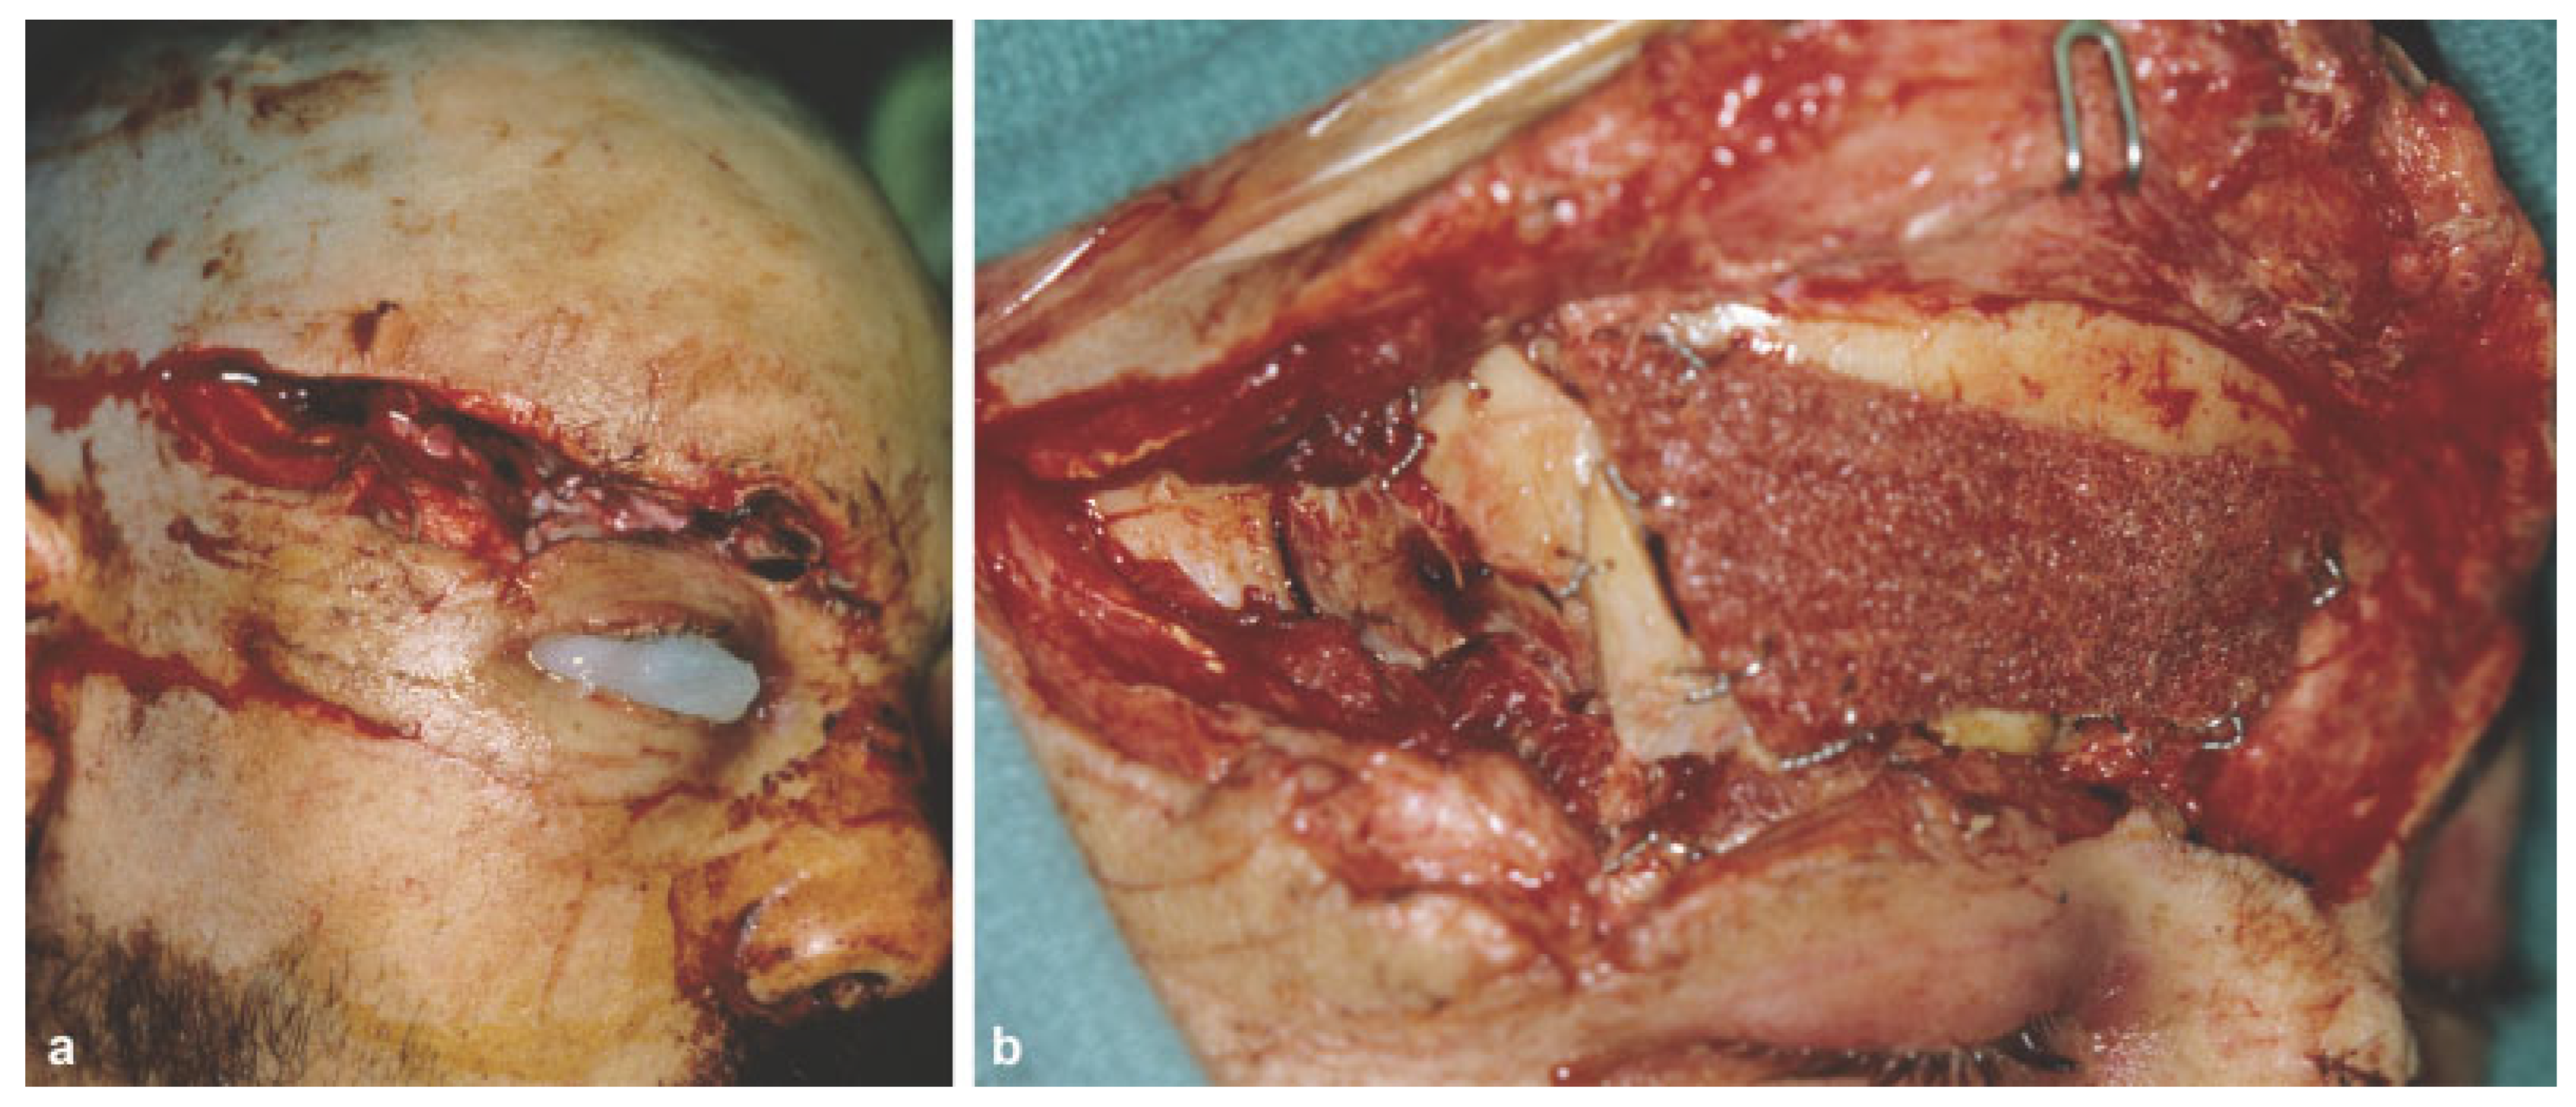

The presence of a supraorbital ridge, glabella, or forehead laceration should raise suspicion for the presence of a frontal sinus fracture (Figure 1). Patients with frontal sinus fractures will often have visible depression in the supraorbital region that accompanies the soft-tissue compromise. Palpation over the suspected injury area may reveal crepitus, instability, and step-off. In patients with significant swelling, however, these physical findings are often masked. Sensory deficits are also common secondary to injury of the supratrochlear and or supraorbital nerves.

Figure 1. (a) Lateral views of a patient with large forehead and glabellar laceration and frontal sinus fracture. (b) Lateral view of the same patient in a following rigid fixation with split calvarial bone graft.